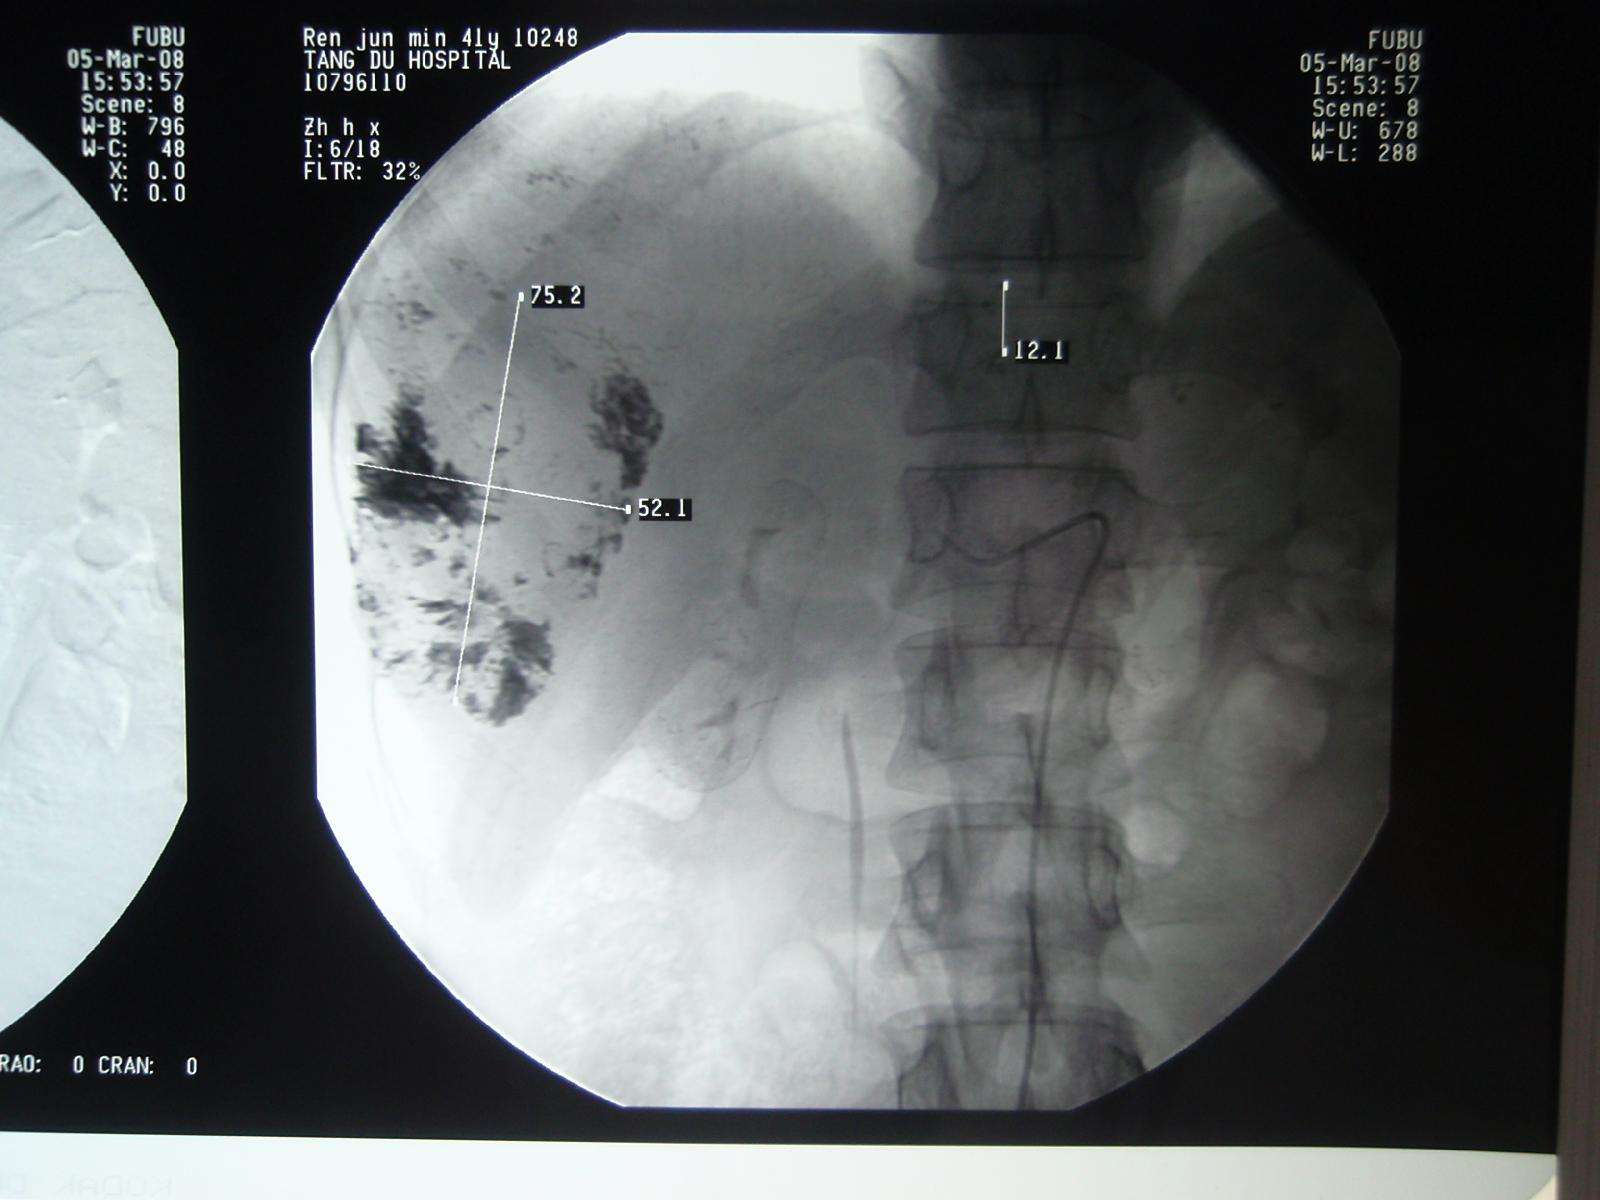

2008年3月5日张洪新教授做介入DSA造影明确诊断:

张洪新教授通过导管用碘化油栓塞瘤血管、中断病灶供血